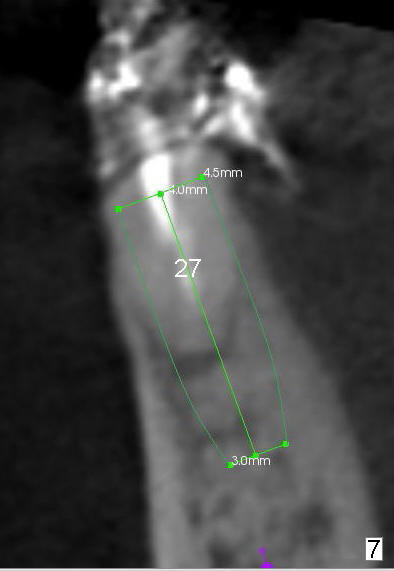

A 85-year-old man has poor dentition (Fig.9). Multiple implants are to be placed at one or two stages (#26-30). If primary stability is obtained for individual implants, they are splinted and immediate provisional is fabricated.

Fig.1-3 are CBCT sagittal sections of the lower right quadrant, whereas Fig.4-8 are coronal sections. The lower left quadrant has been restored.

The sockets of #27,28 will be treated with 2% Xylocaine/1.:50,000 Epinephrine as control group of the antibiotic study.